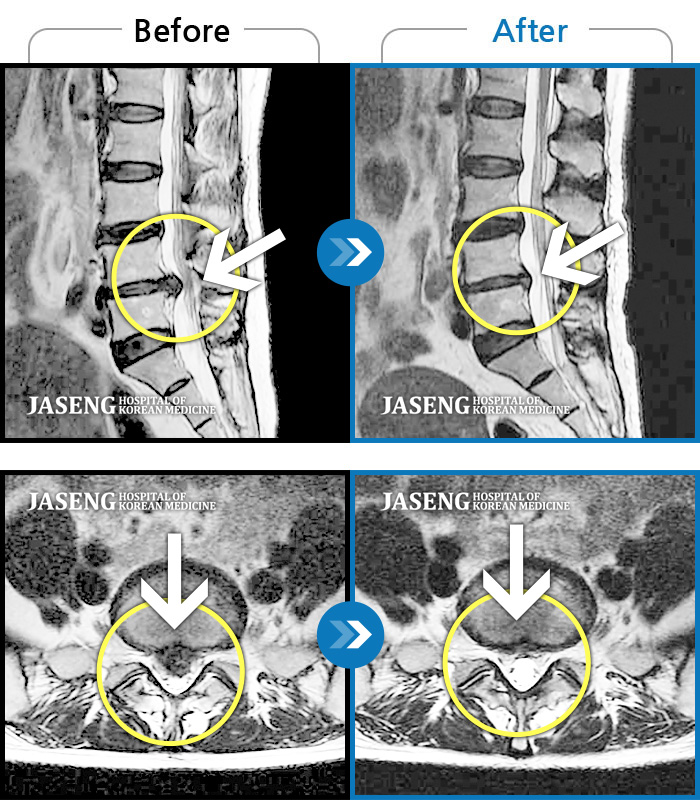

MRI로 보는 치료결과

60건의 MRI 전후 사진으로 터진 디스크 흡수 사례를 확인하세요.

※ 환자분에게 사전 동의를 받아 동일 조건에서 촬영되었으며, 개인에 따라 치료 후 부작용이 발생할 수도 있으니 사전에 의료진과 상담 후 치료를 진행하시기 바랍니다.